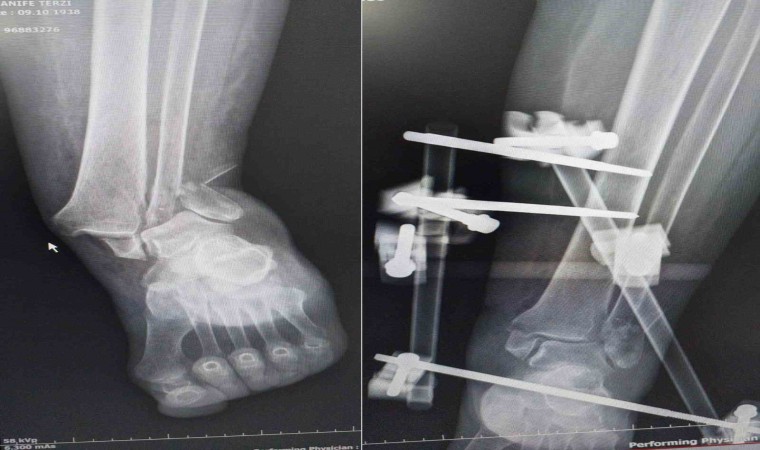

Adıyaman’da 86 yaşındaki H.T., ayak bileğindeki kırıklar nedeniyle Kahta Devlet Hastanesi’ne başvurdu. Ameliyat sırasında narkoz kullanılması durumunda hayati riskler ortaya çıkabileceğinden, hastaya narkozsuz bir ameliyat önerildi. H.T., Ortopedi Uzmanı Op. Dr. İbrahim Halil Cebe tarafından Kahta’da ilk kez Walant Tekniği kullanılarak narkozsuz bir şekilde başarılı bir ameliyat geçirdi.